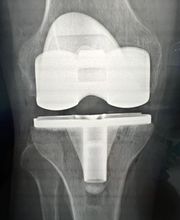

Il Dottor Pera Antonio esercita la professione medica presso il proprio studio ubicato a La Spezia, dove riceve su appuntamento. Pera dr. Antonio è medico chirurgo specializzato in Ortopedia e Traumatologia, anche infantile. Pera dr. Antonio è attualmente iscritto alla S.I.O.T.(Società Italiana di ortopedia e traumatologia); S.I.A.(Società italiana di artroscopia) di cui risulta essere socio onorario; A.L.A.(Associazione ligure di artroscopia); S.I.T.R.A.S.(Società italiana di traumatologia dello sport); S.P.L.L.O.T.(Società piemontese ligure e lombarda di ortopedia e traumatologia); Club di Chirurgia del ginocchio. Dal Gennaio 2012 Pera dr. Antonio svolge il ruolo di Delegato Regionale S.I.A.(Società Italiana di Artroscopia) per la Liguria. Riceve solo su appuntamento.